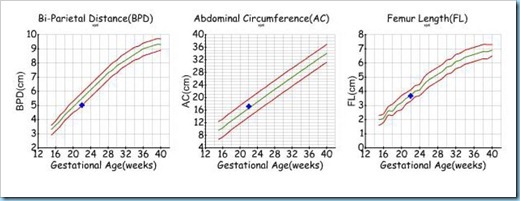

2013/03/01:產檢20W+4D..小朋友385g標準!!

Mama體重54.1Kg..小寶寶右腎0.83~左腎0.53cm~皆要追蹤!!!哎~~